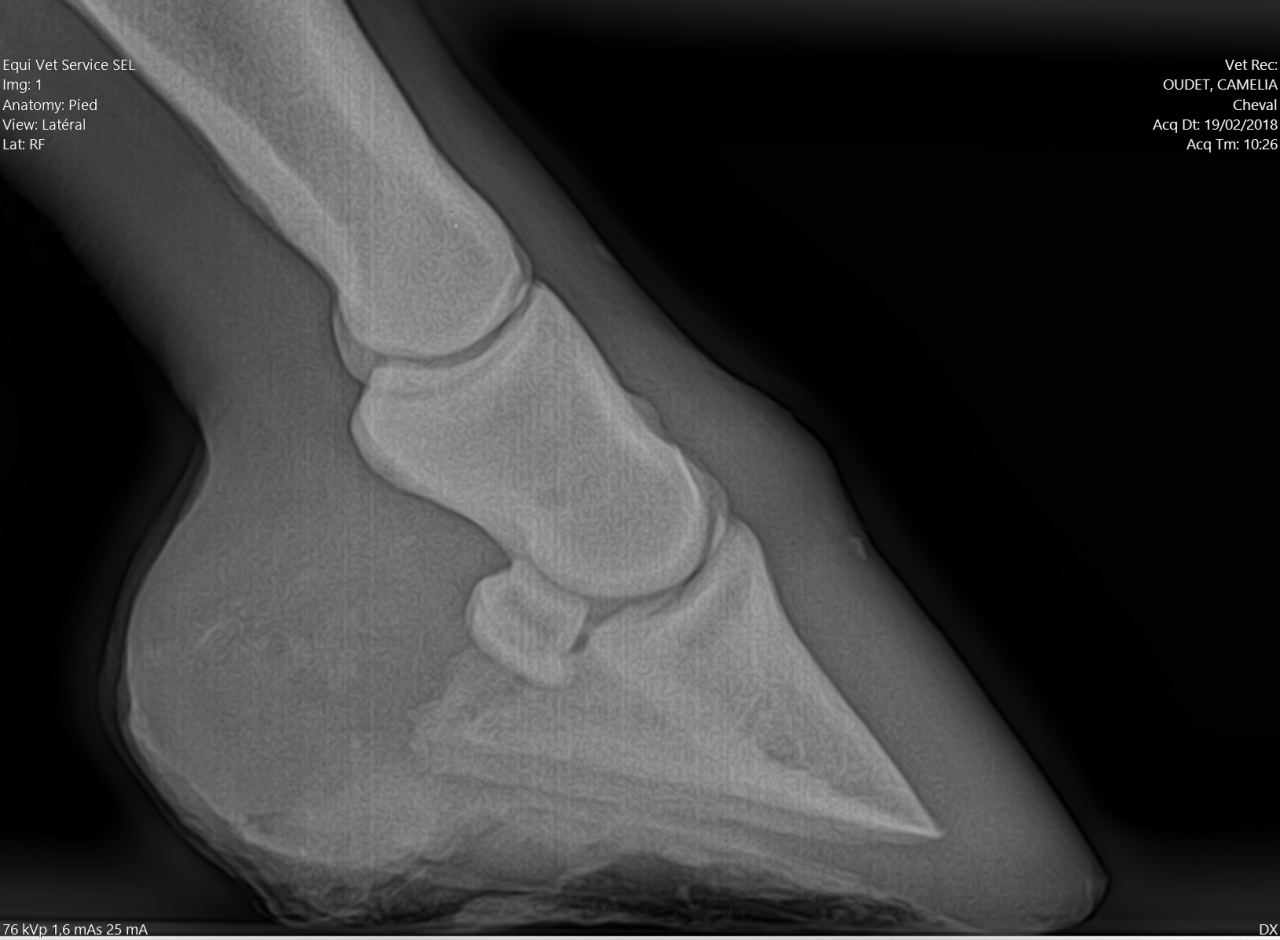

| Dire merci | Alors pour les fers, je ne suis pas une ayatollah du pieds nus, donc je l'ai évoqué avec la véto. Selon elle à ce stade, ça ferait plus de mal que de bien, pour les raisons suivantes : - jument confortable au pré, puisque terrains bien mous en ce moment - difficulté à ferrer vu ce qu'il "reste de pied", elle pense que ça va être un calvaire pour la jument de clouer - si jamais c'est un soucis de vascularisation, ça va plutôt amplifer le soucis Concernant les PHW, justement avec Kaline on était passé à une orthopédie à base de PHW, parce que pas moyen de faire tenir des fers compensés en talon dans la boue. Après ça dépend beaucoup de la locomotion du cheval, mais vu que Cam' n'est pas une foudre de guerre et que même si le pré est boueux on ne s'enfonce pas tant que ça, je suis plutôt confiante. Pour la biotine je veux bien des infos. Moi on m'a souvent dit que ça rendait l'organisme "paresseux" pour en produire lui même, et que si la flore digestive et les apports nutritionnels sont ok y a pas de raison d'avoir de carence ? J'aurais donc plutôt tendance à agir là dessus ? Les radios en spoilers pour celles et ceux que ça intéresse. Message édité le 19/02/18 à 17:18 |

| Dire merci | Il n’y a aucune sole dessus , tu m’étonnes qu’elle ait mal la jument ... Pour clouer en brochant bas aucun soucis et sinon Coller. Mais le temps que l’inflammation parte ... Tu parles de PHW c’est quoi ? |

| Dire merci | Elle a des radios moins pire que le mien quand même, et pourtant le MF n'a eu aucun mal à la ferrer ![]() Il a juste broché haut, et pas de raison qu'il y ait de douleurs au ferrage ![]() Par contre, le mien avait les pieds moins petits que la petite en proportion, et pourtant il me parait plus fin... |